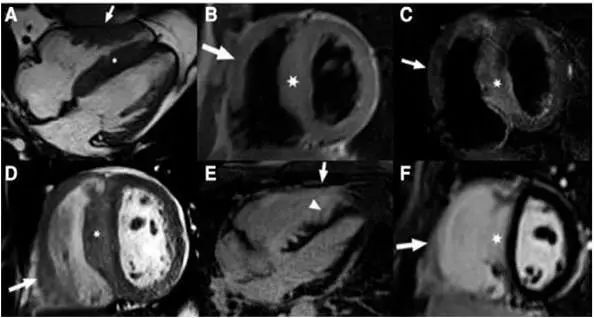

3.心脏磁共振成像

心脏磁共振成像较超声心动图提供的信息更多。钆对比剂延迟强化 (1ate gadolinium enhancement,LGE)是识别心肌纤维化最有效的方法,LGE与死亡、SCD等风险正相关。约65%的HCM患者出现LGE,多表现为肥厚心肌内局灶性或斑片状强化,以室间隔与右心室游离壁交界处局灶状强化最为典型。

4.超声心动图检查

显示左心室壁显著增厚,心室间隔较心室后壁更为肥厚,左心室腔小,流出道狭窄和心脏收缩时二尖瓣前瓣叶向前移位(SAM征)。

超声心动图